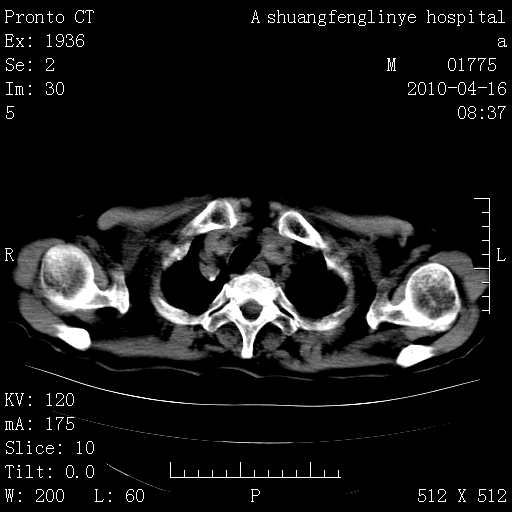

标题: CT25784:咳痰、请会诊!结核? [打印本页]

标题: CT25784:咳痰、请会诊!结核?

陈旧性结核,胃腔扩大,脾脏受压后移

老年肺间质纤维化,肺动脉高压-----肺心病。

慢支肺气肿,左上陈旧性结核,主动脉冠脉钙化

典型 夹层动脉瘤。 内膜瓣钙化移位